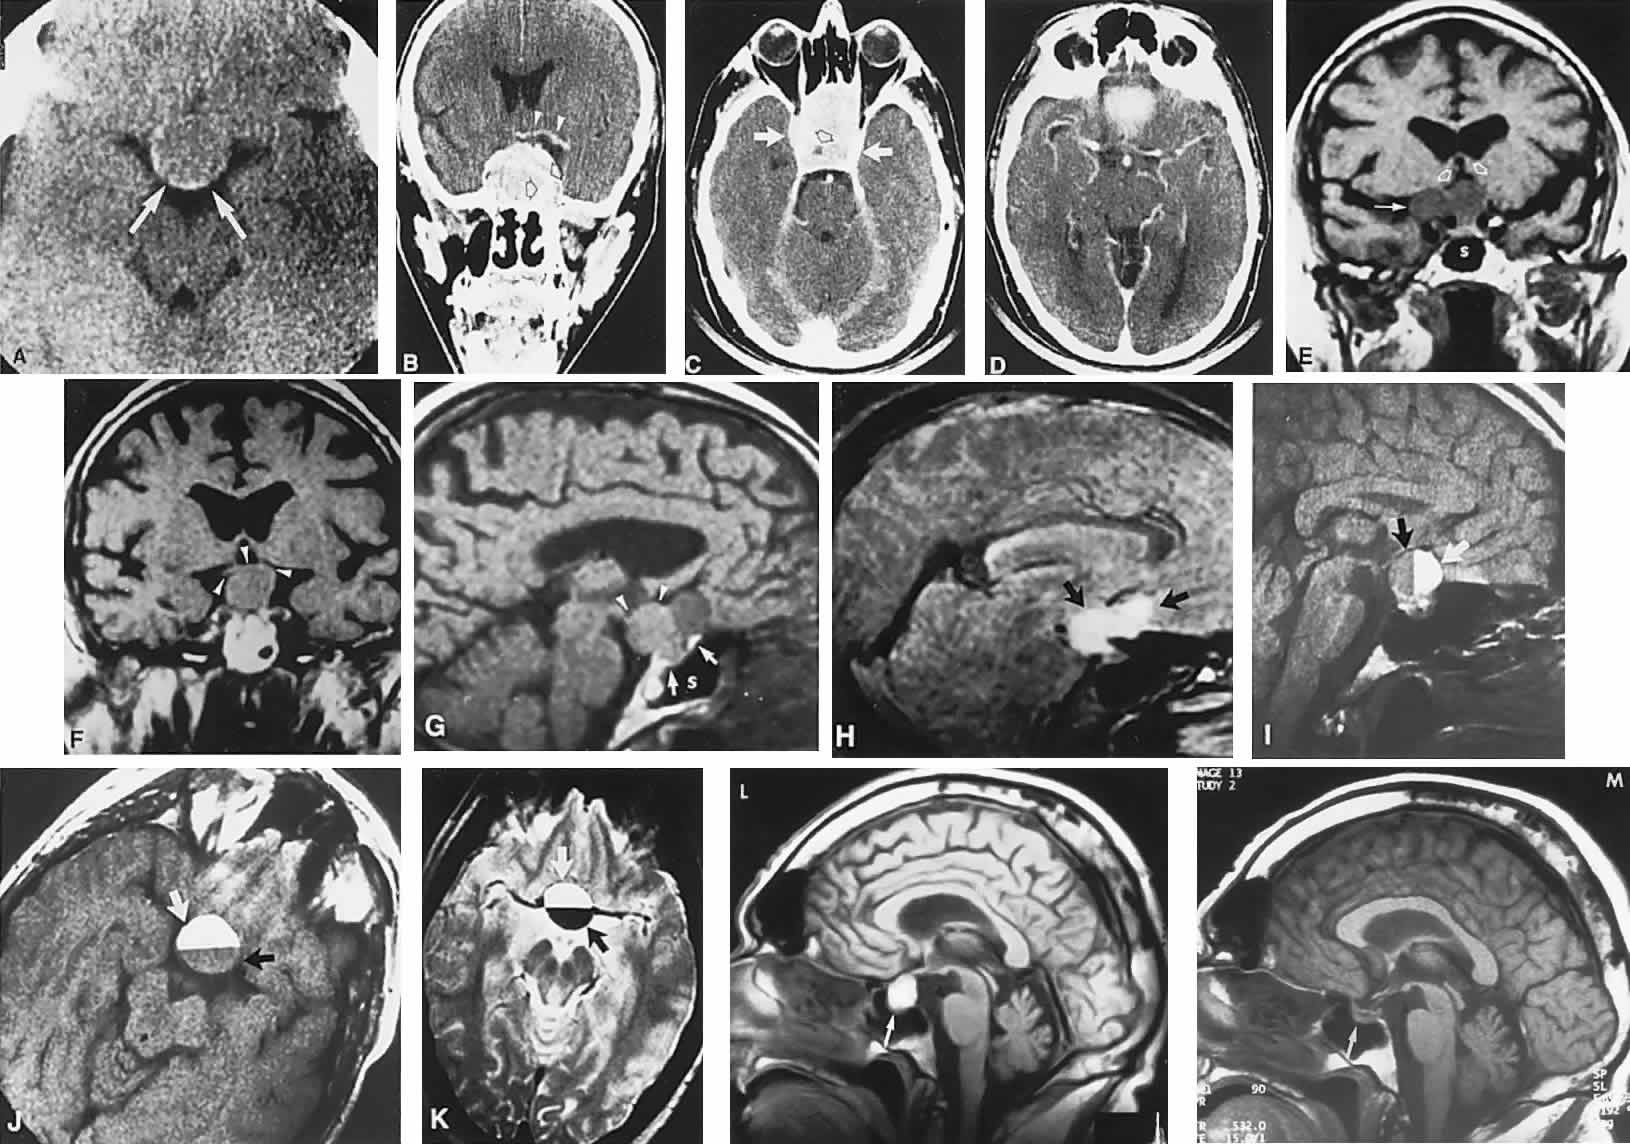

Fig. 2. Large prolactinoma. Original vision in the right eye (RE) was 8/200, left eye (LE) 1/200, with serum prolactin of 26,000 ng/ml and galactorrhea. Four months of bromocriptine reduced prolactin to 661 ng/ml, vision improved to RE 20/40, LE 20/50. At 3 years, vision was as follows: RE 20/30, LE 20/20; prolactin was 25.9 ng/ml. Enhanced magnetic resonance imaging. Sagittal (A) and coronal (C) images at diagnosis. Sagittal (B) and coronal (D) images at 2-year follow-up, showing dramatic shrinkage of the mass.